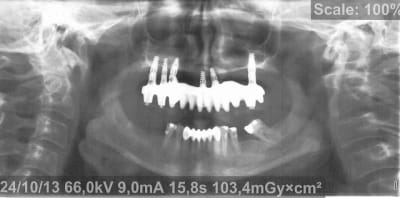

Voici donc les panos pour vos petits yeux ébahis

Profitez bien : elles sont ds l ordre chronologique...

(On est loin de tout comprendre sur les panos un peu floue, si ce n'est qu'à la fin totu est perdu)

Je vous donne une petite info : le comblement au BioOss a échoué largement...et on lui propose des greffes crâniennes à présent

Qu en pensez vous ??????????

- On y voit un manque flagrant de densité du greffon

- On y voit une perte d'un implant sans changement de plan de traitement, on se retrouve avec un seul implant du coté où mastique le patient

- On y voit une armature qui baille sur le seul implant qui reste secteur 2, et donc manque de passivité

- On y voit ce qui devait arriver,

Mais je vois aucun rapport entre l’échec et la nature du matériau mis en place dans le sinus....

mais tu vas nous montrer ;)